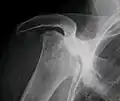

Radiografía de una osteonecrosis total de la cabeza del húmero derecho. Mujer de 81 años de edad con diabetes de larga evolución. -